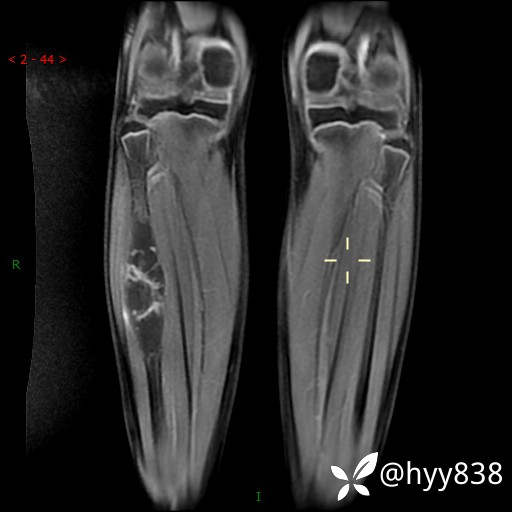

MRI 增强(cor+sag+axi)